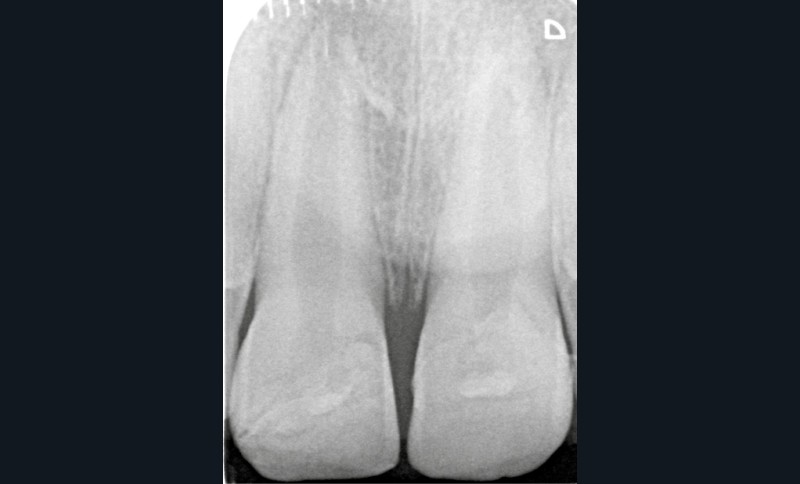

À 3 mois, sur la radiographie (fig. 9) l’apex semble se fermer et les tests de sensibilité sont toujours positifs. De la plaque dentaire (fig. 10) est observée. Une motivation à l’hygiène à l’aide d’un révélateur de plaque est réalisée. Par crainte, les enfants (ou les parents pour les plus jeunes) évitent fréquemment le brossage des dents traumatisées ; des gingivites peuvent être secondaires à ce défaut d’hygiène dans un contexte déjà inflammatoire consécutivement au traumatisme. Une attention particulière doit donc être portée à l’hygiène bucco-dentaire du patient.

A chaque séance, un contrôle radiographique devra être réalisé afin de vérifier l’apexogenèse de 11 et 21 et l’absence de lésion radio-claire apicale. Un test de sensibilité sera également réalisé à l’aide d’un coton froid imprégné grâce au cryospray. Les dents controlatérales seront également testées comme comparatifs des dents traumatisées.